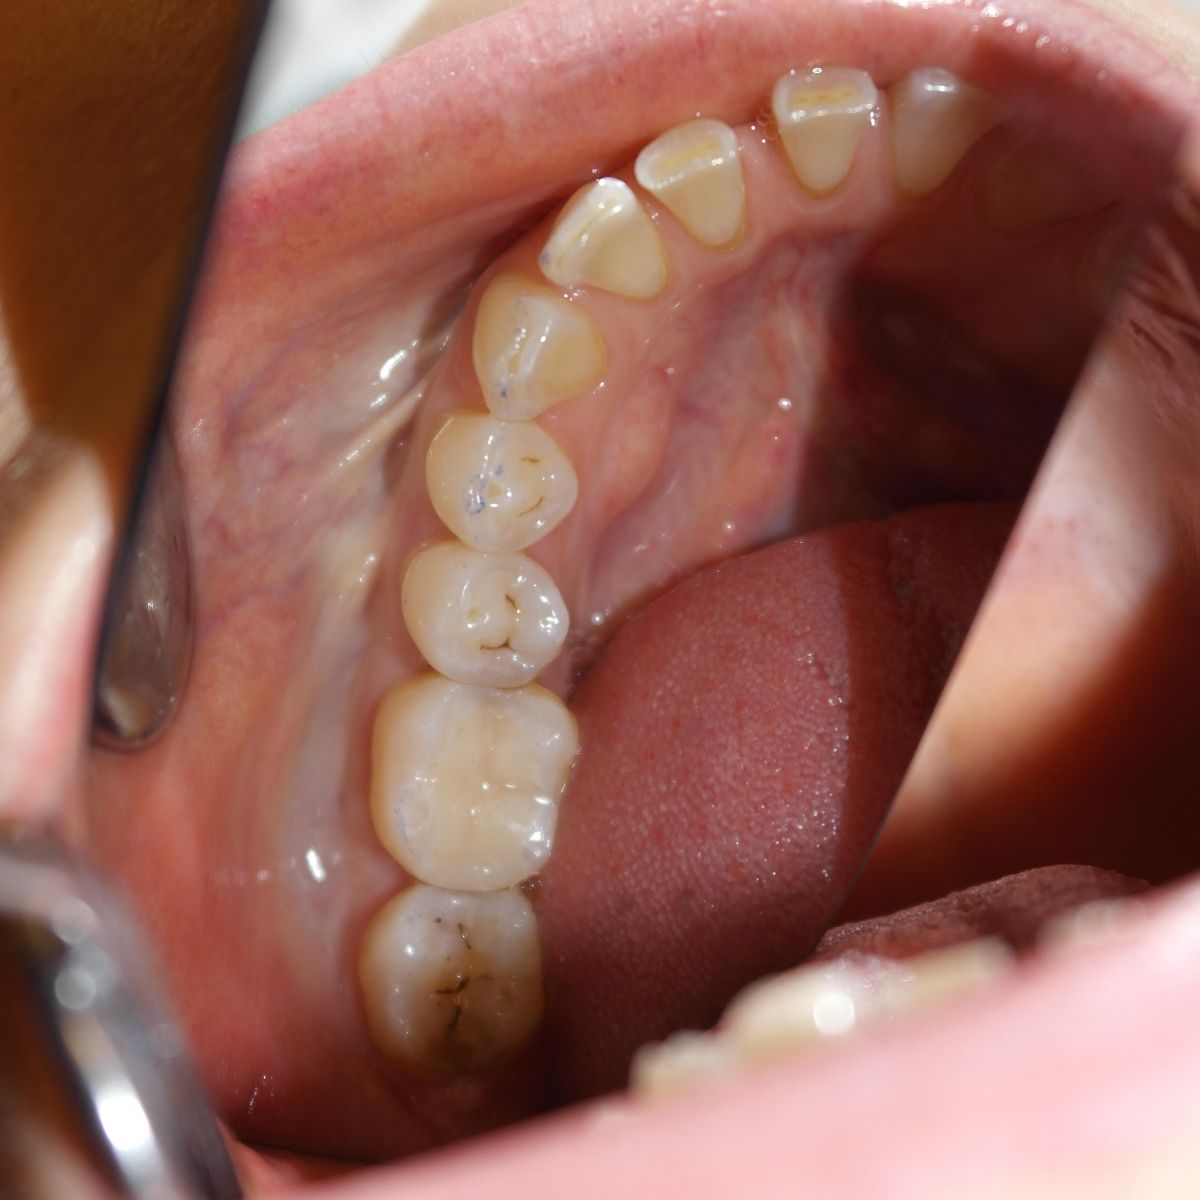

Esztétikus, kompozit tömések

Az esztétikai fogászat a töméseket minden esetben fémmentes, általában fényre kötő tömőanyagból készíti, amely segítségével a fogakkal megegyező színű, természethű hatás és tartós eredmény érhető el.

Az esztétikus tömések készítése során ún. kompozit (kerámia szemcsékkel töltött műanyag) tömőanyagokat használunk, melyek legfőbb előnye a kiváló esztétikai hatás. Ezenkívül kevesebb foganyag feláldozását teszik szükségessé az előkészítés során, bizonyos esetekben pedig fúrás nélkül is lehetséges a sérült fogfelszínek javítása, vagy a fogak formai korrekciója.

- A fogüreget megtöltjük a választott színű töltőanyaggal.

- Ezután kialakítjuk a fog csúcsait és barázdáit.

- A stabil kötések kialakítása érdekében a rétegeket polimerizációs lámpával világítjuk meg, így a polimer fogtömés tökéletesen beépül a fogüregbe.

- Ezután a fogtömés felszínét lepolírozzuk, hogy a természetes foggal megegyező felszínt kapjunk.